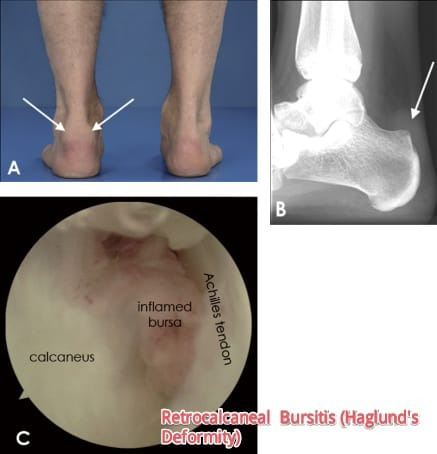

It is a bony enlargement on the back of the heel that most often leads to painful bursitis, which is an inflammation of the bursa (a fluid-filled sac between the tendon and bone). In Haglund’s deformity, the soft tissue near the Achilles tendon becomes irritated when the bony enlargement rubs against shoes.Haglund’s deformity can occur in one or both feet.

To some extent, heredity plays a role in Haglund’s deformity. People can inherit a type of foot structure that makes them prone to developing this condition. For example, high arches can contribute to Haglund’s deformity. The Achilles tendon attaches to the back of the heel bone, and in a person with high arches, the heel bone is tilted backward into the Achilles tendon. This causes the uppermost portion of the back of the heel bone to rub against the tendon. Eventually, due to this constant irritation, a bony protrusion develops and the bursa becomes inflamed. It is the inflamed bursa that produces the redness and swelling associated with Haglund’s deformity. A tight Achilles tendon can also play a role in Haglund’s deformity, causing pain by compressing the tender and inflamed bursa. In contrast, a tendon that is more flexible results in less pressure against the painful bursa. Another possible contributor to Haglund’s deformity is a tendency to walk on the outside of the heel. This tendency, which produces wear on the outer edge of the sole of the shoe, causes the heel to rotate inward, resulting in a grinding of the heel bone against the tendon. The tendon protects itself by forming a bursa, which eventually becomes inflamed and tender.

After evaluating the patient’s symptoms, the foot and ankle surgeon will examine the foot. In addition, x-rays will be requested to help the surgeon evaluate the structure of the heel bone.

If non-surgical treatment fails to provide adequate pain relief, surgery may be needed consisting of debridement of the affected Achilles tendon and excision of the retrocalcaneal bursa and the Haglund deformity. It can be done through Arthroscopic surgery or through mini open technique.